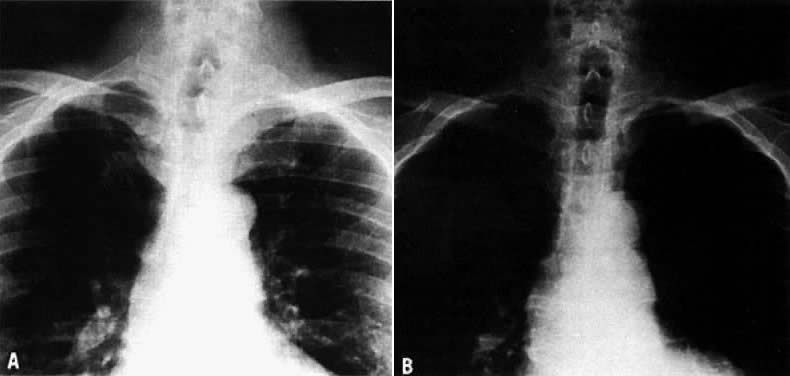

On physical examination, an asymptomatic neck mass is a presenting sign in more than 90% of patients. Cervical lymph nodes, cord paralysis, pain, or dysphagia may indicate thyroid carcinoma. Deviation of the trachea demonstrated on an x-ray is not always an indication of malignancy. A cystic lesion can produce a deviation of the trachea that resolves after aspiration of the fluid (Fig. 2). More than 90% of patients with thyroid nodules are clinically and chemically euthyroid. A little fewer than 10% may have an autonomous or hyperfunctioning nodule evident on a scintigraphic scan, in which case the patient may show symptoms of hyperthyroidism.50

Fig. 2. Single cold nodule of the left lobe of the thyroid gland. Routine chest x-ray demonstrates deviation of the trachea. A. Fine-needle aspiration obtained 7 mL of clear fluid. The cytology was benign. B. Repeat chest x-ray approximately 6 months later demonstrates complete resolution of the indentation of the left side of the trachea. The diagnosis was cystic adenomatoid nodule.